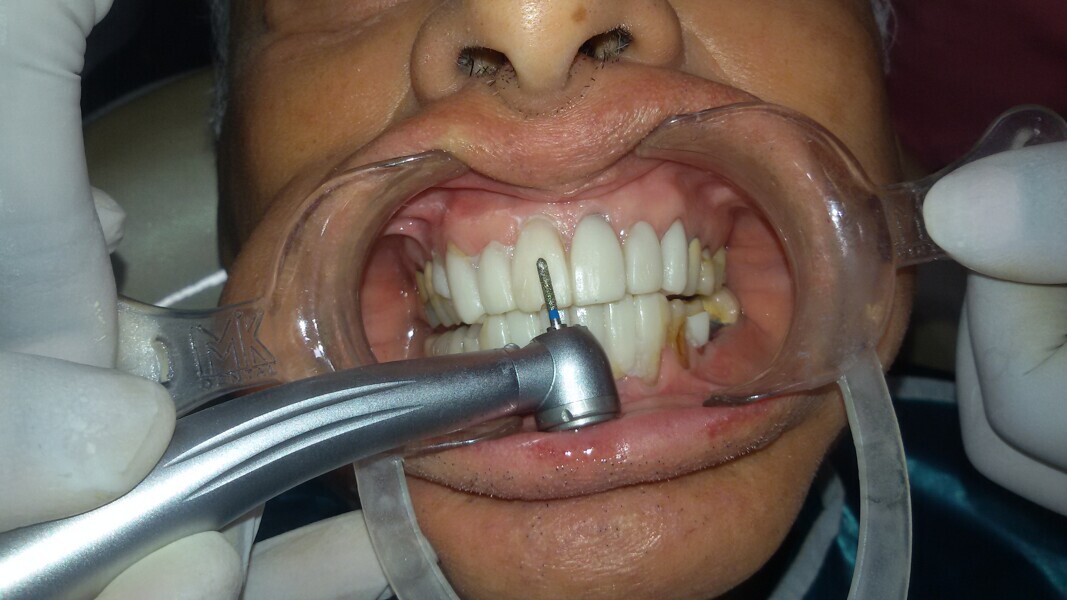

Figure 18 Preparationn through test drive or provisionals